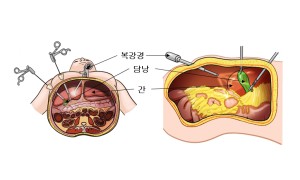

추적 검사 중에 용종의 크기가 커지면 담낭 절제술을 통해 담낭과 용종을 함께 제거합니다. 담낭 용종의 수술적 치료는 용종의 크기와 자라는 속도, 환자의 나이, 동반된 담낭의 다른 이상 소견, 수술의 위험성 등을 고려하여 결정합니다.